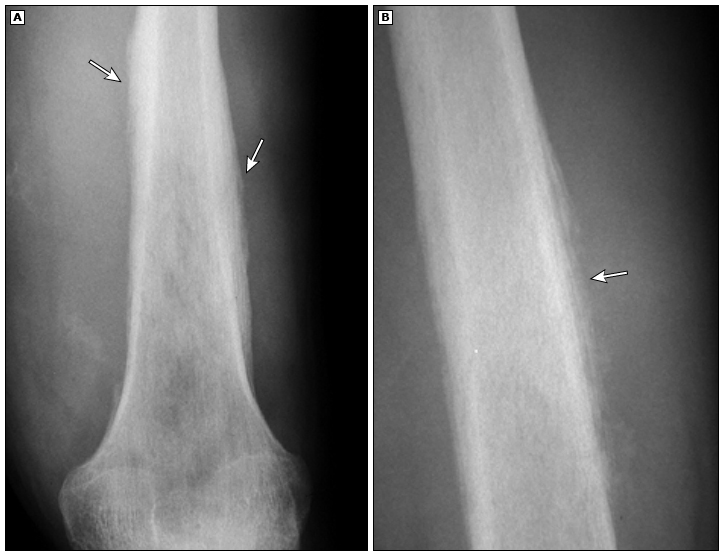

影像学检查(X光片、CT、核磁共振): 这是最直接的“雷达扫描”,三种检查通过互相参考,可以明确评估肿瘤的大小、位置和破坏范围。骨肉瘤和尤文肉瘤在片子上常常可以看到明确的骨质破坏,骨肉瘤可以在X光片上看到Codman三角、日光放射影等等的表现,而尤文肉瘤在X光片上有时会出现像“洋葱皮”一样的特殊表现,这些都是帮助医生发现它们的重要线索。此外,胸部CT扫描在诊断肺转移方面尤其重要,因为肺是骨肉瘤、尤文肉瘤最常见的转移部位。

图2 骨肉瘤和尤文肉瘤的典型X线表现